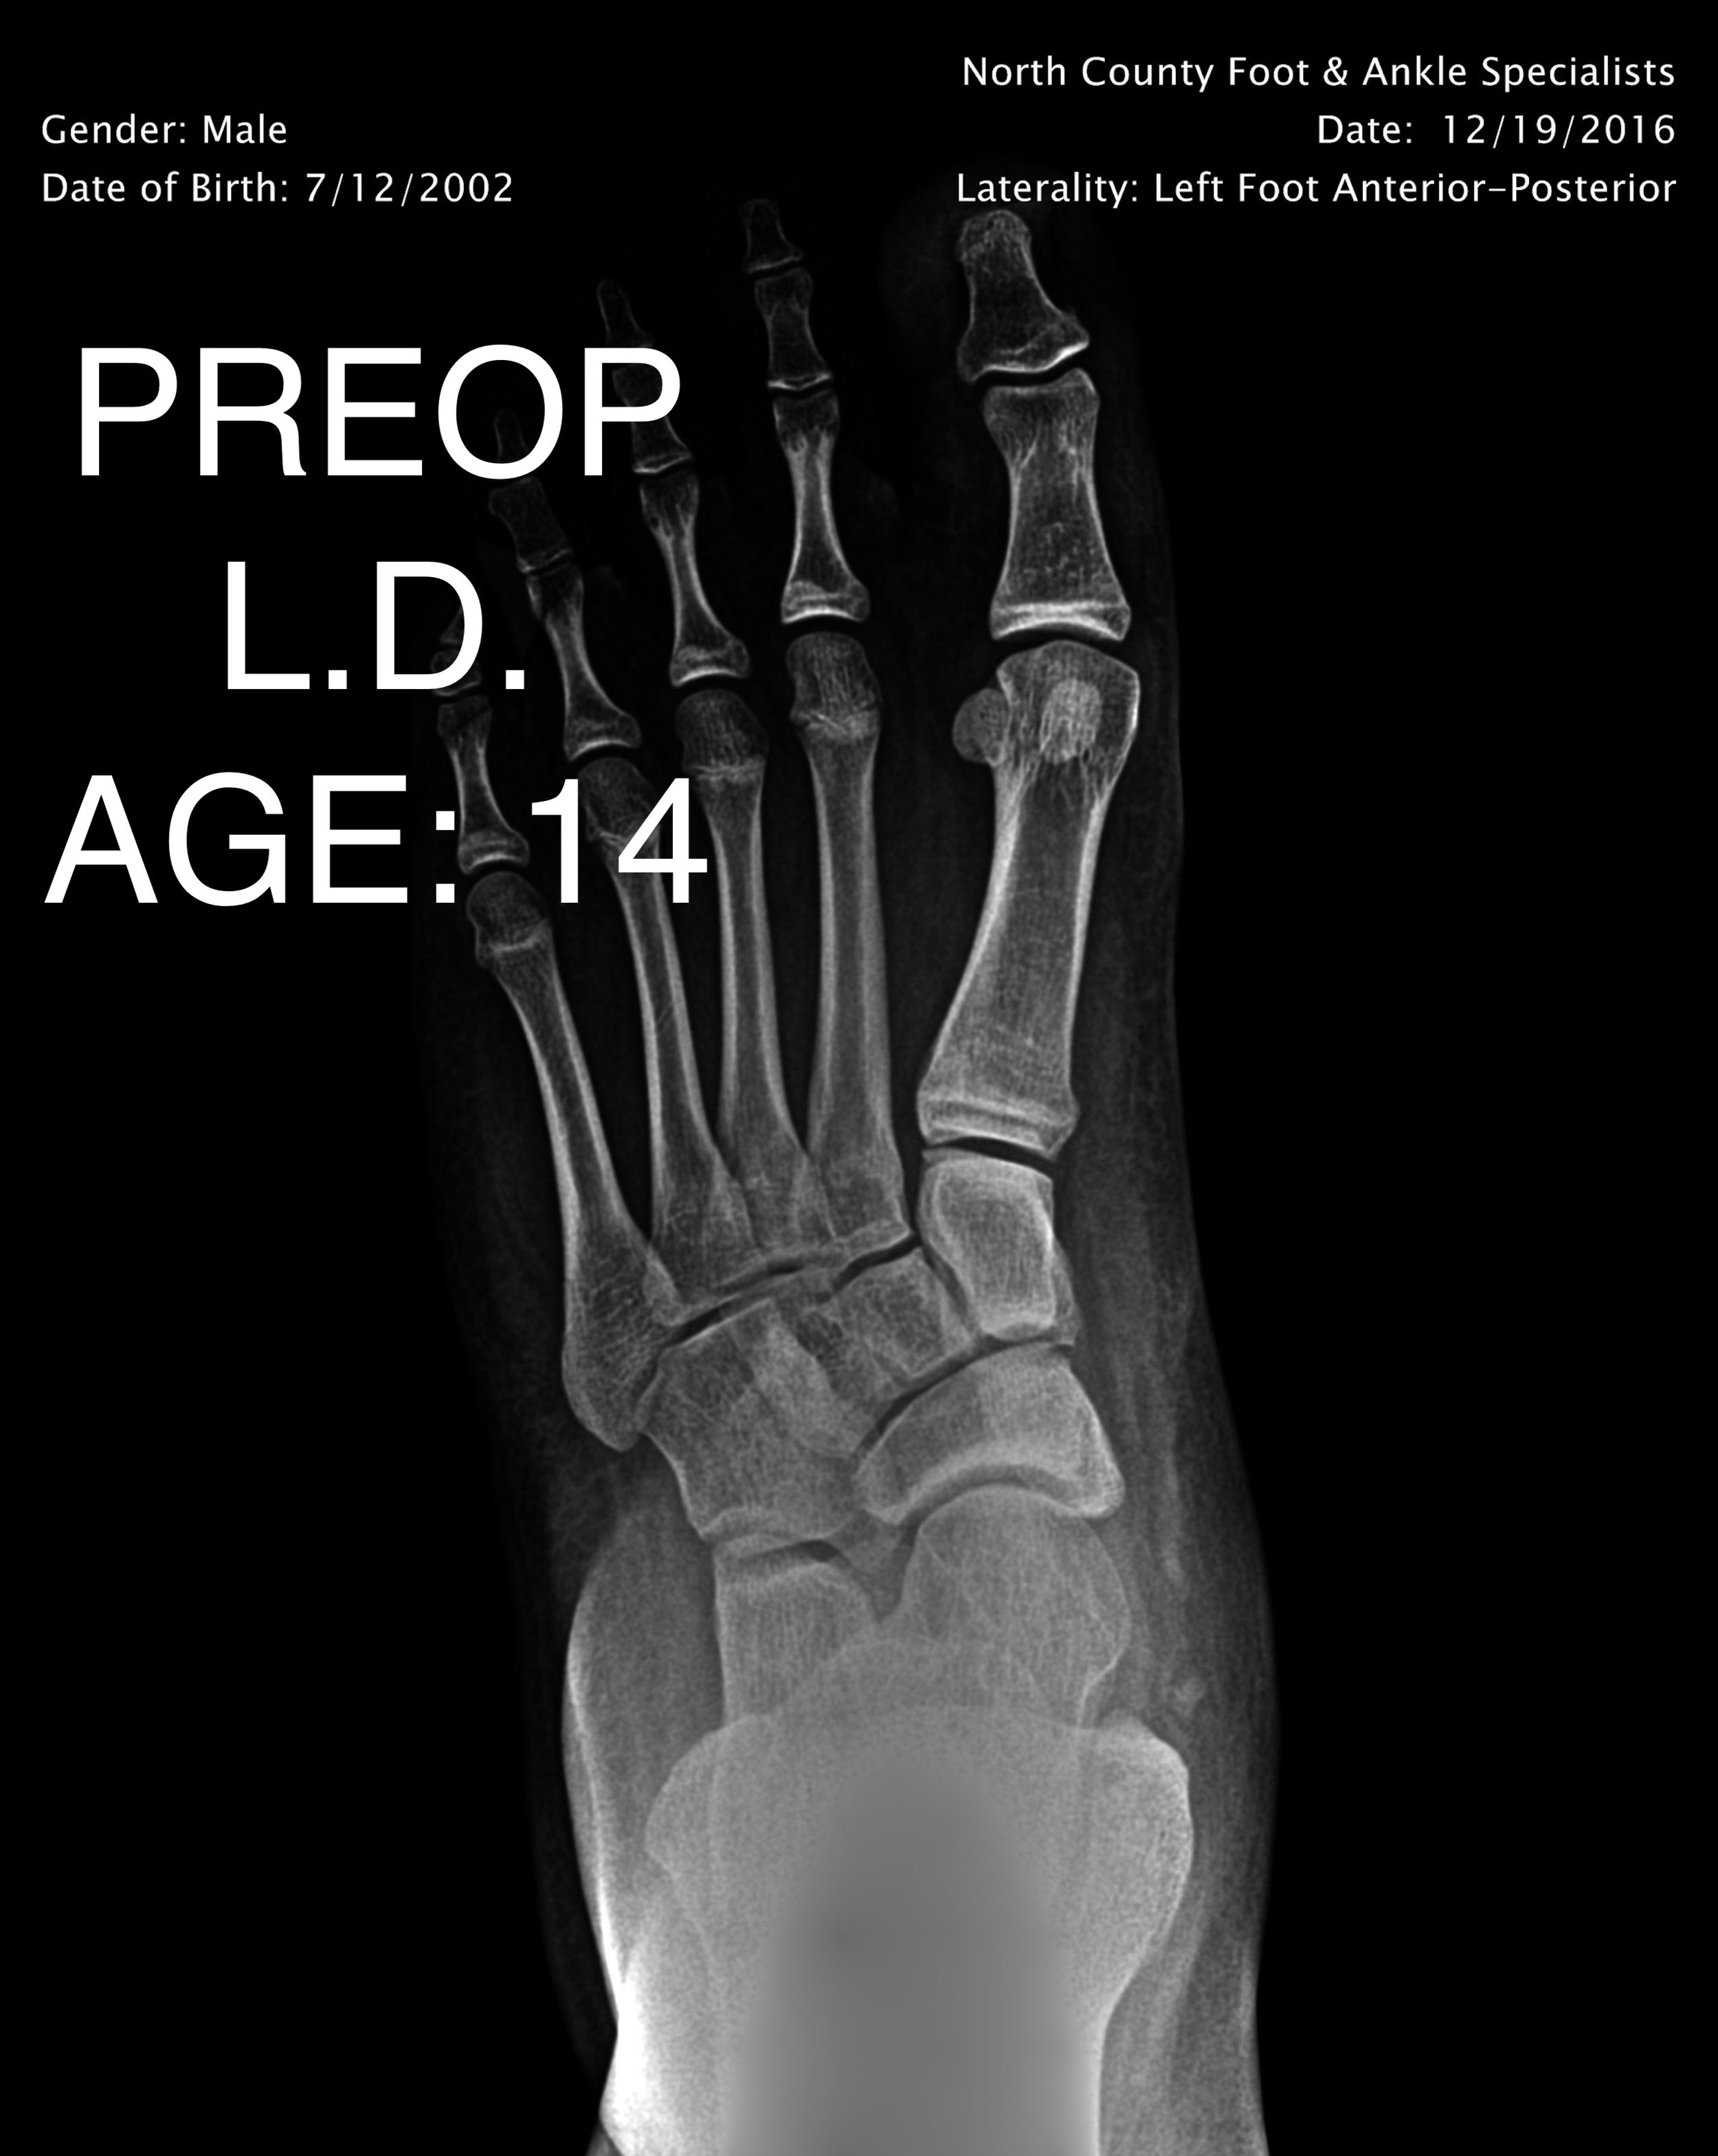

PEDIATRIC FLAT FOOT